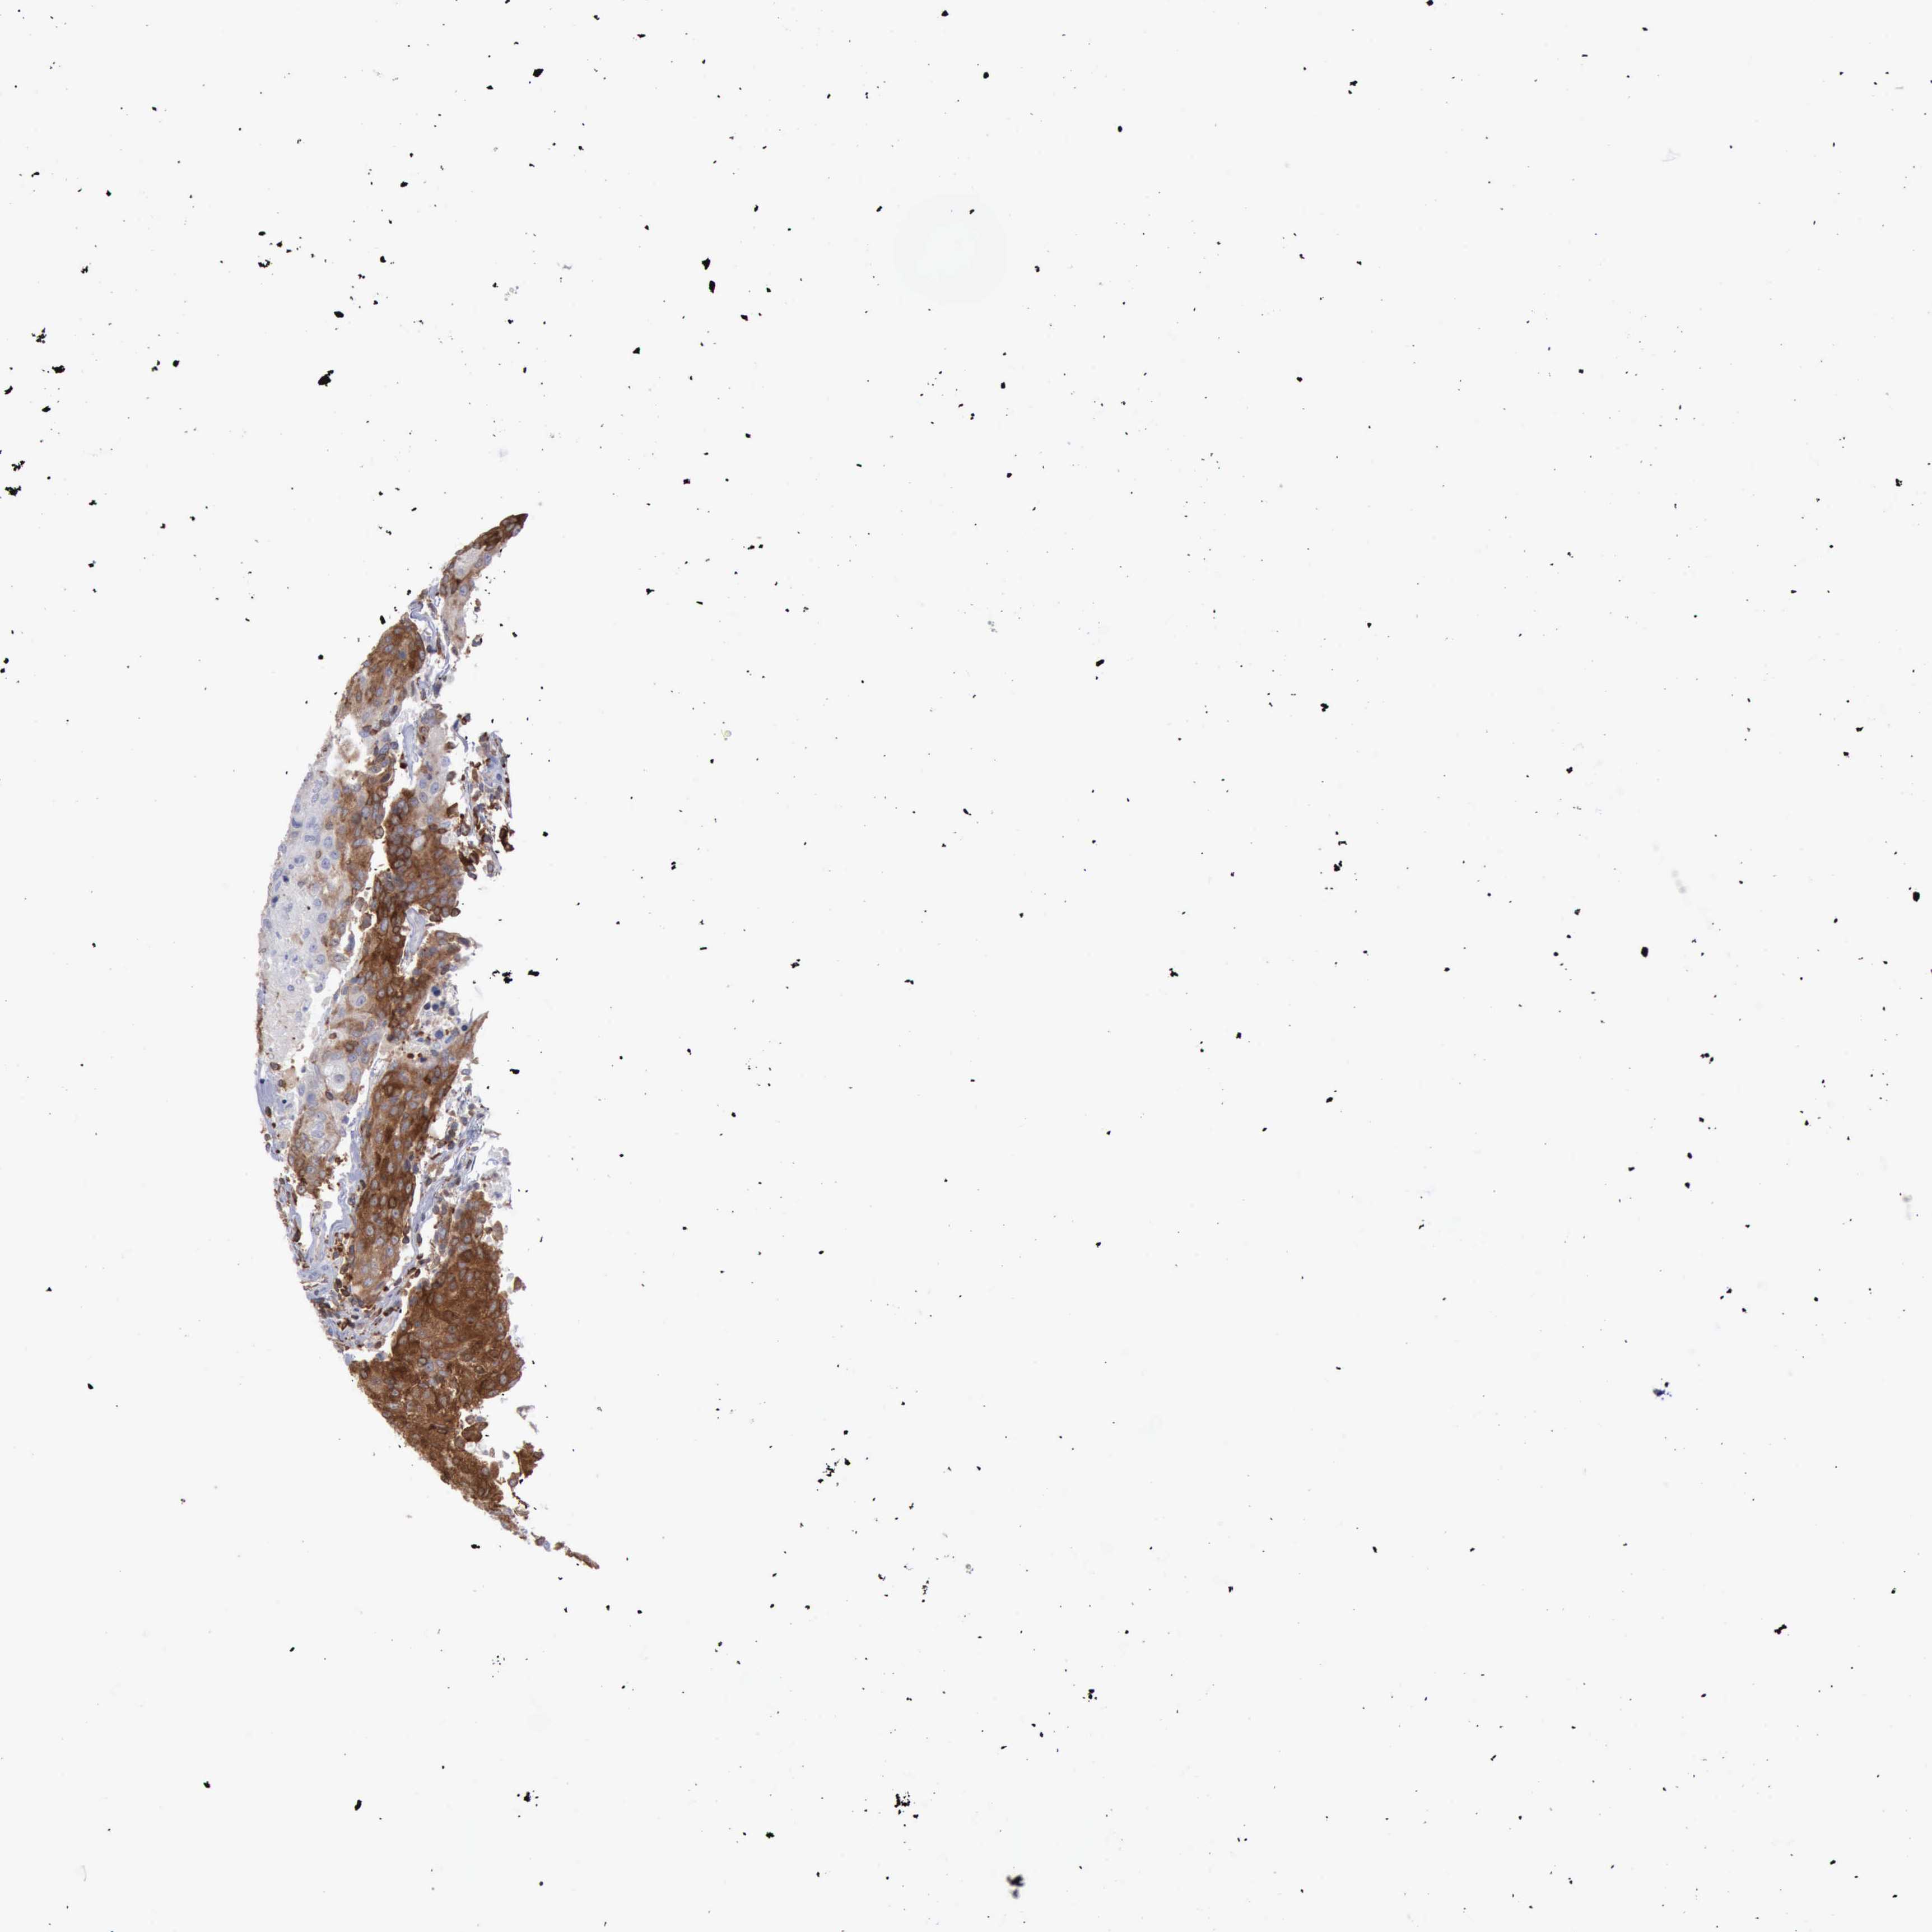

UROTHELIAL CANCER - Protein expressioni

A mouse-over function shows sample information and annotation data. Click on an image to view it in a full screen mode. Samples can be filtered based on level of antibody staining by selecting one or several of the following categories: high, medium, low and not detected. The assay and annotation is described here.

Note that samples used for immunohistochemistry by the Human Protein Atlas do not correspond to samples in the TCGA dataset.

Antibody stainingi

Antibody staining in the annotated cell types in the current human tissue is reported as not detected, low, medium, or high, based on conventional immunohistochemistry profiling in selected tissues. This score is based on the combination of the staining intensity and fraction of stained cells.

Each image is clickable and will lead to virtual microscopy that enables deeper exploration of all samples and also displays staining intensity scores, fraction scores and subcellular localization as well as patient and tissue information for each sample.

Antibody HPA001032

Antibody HPA027214

Antibody CAB037024

Urothelial carcinoma, High grade

Urothelial carcinoma, Low grade

Urothelial carcinoma, NOS